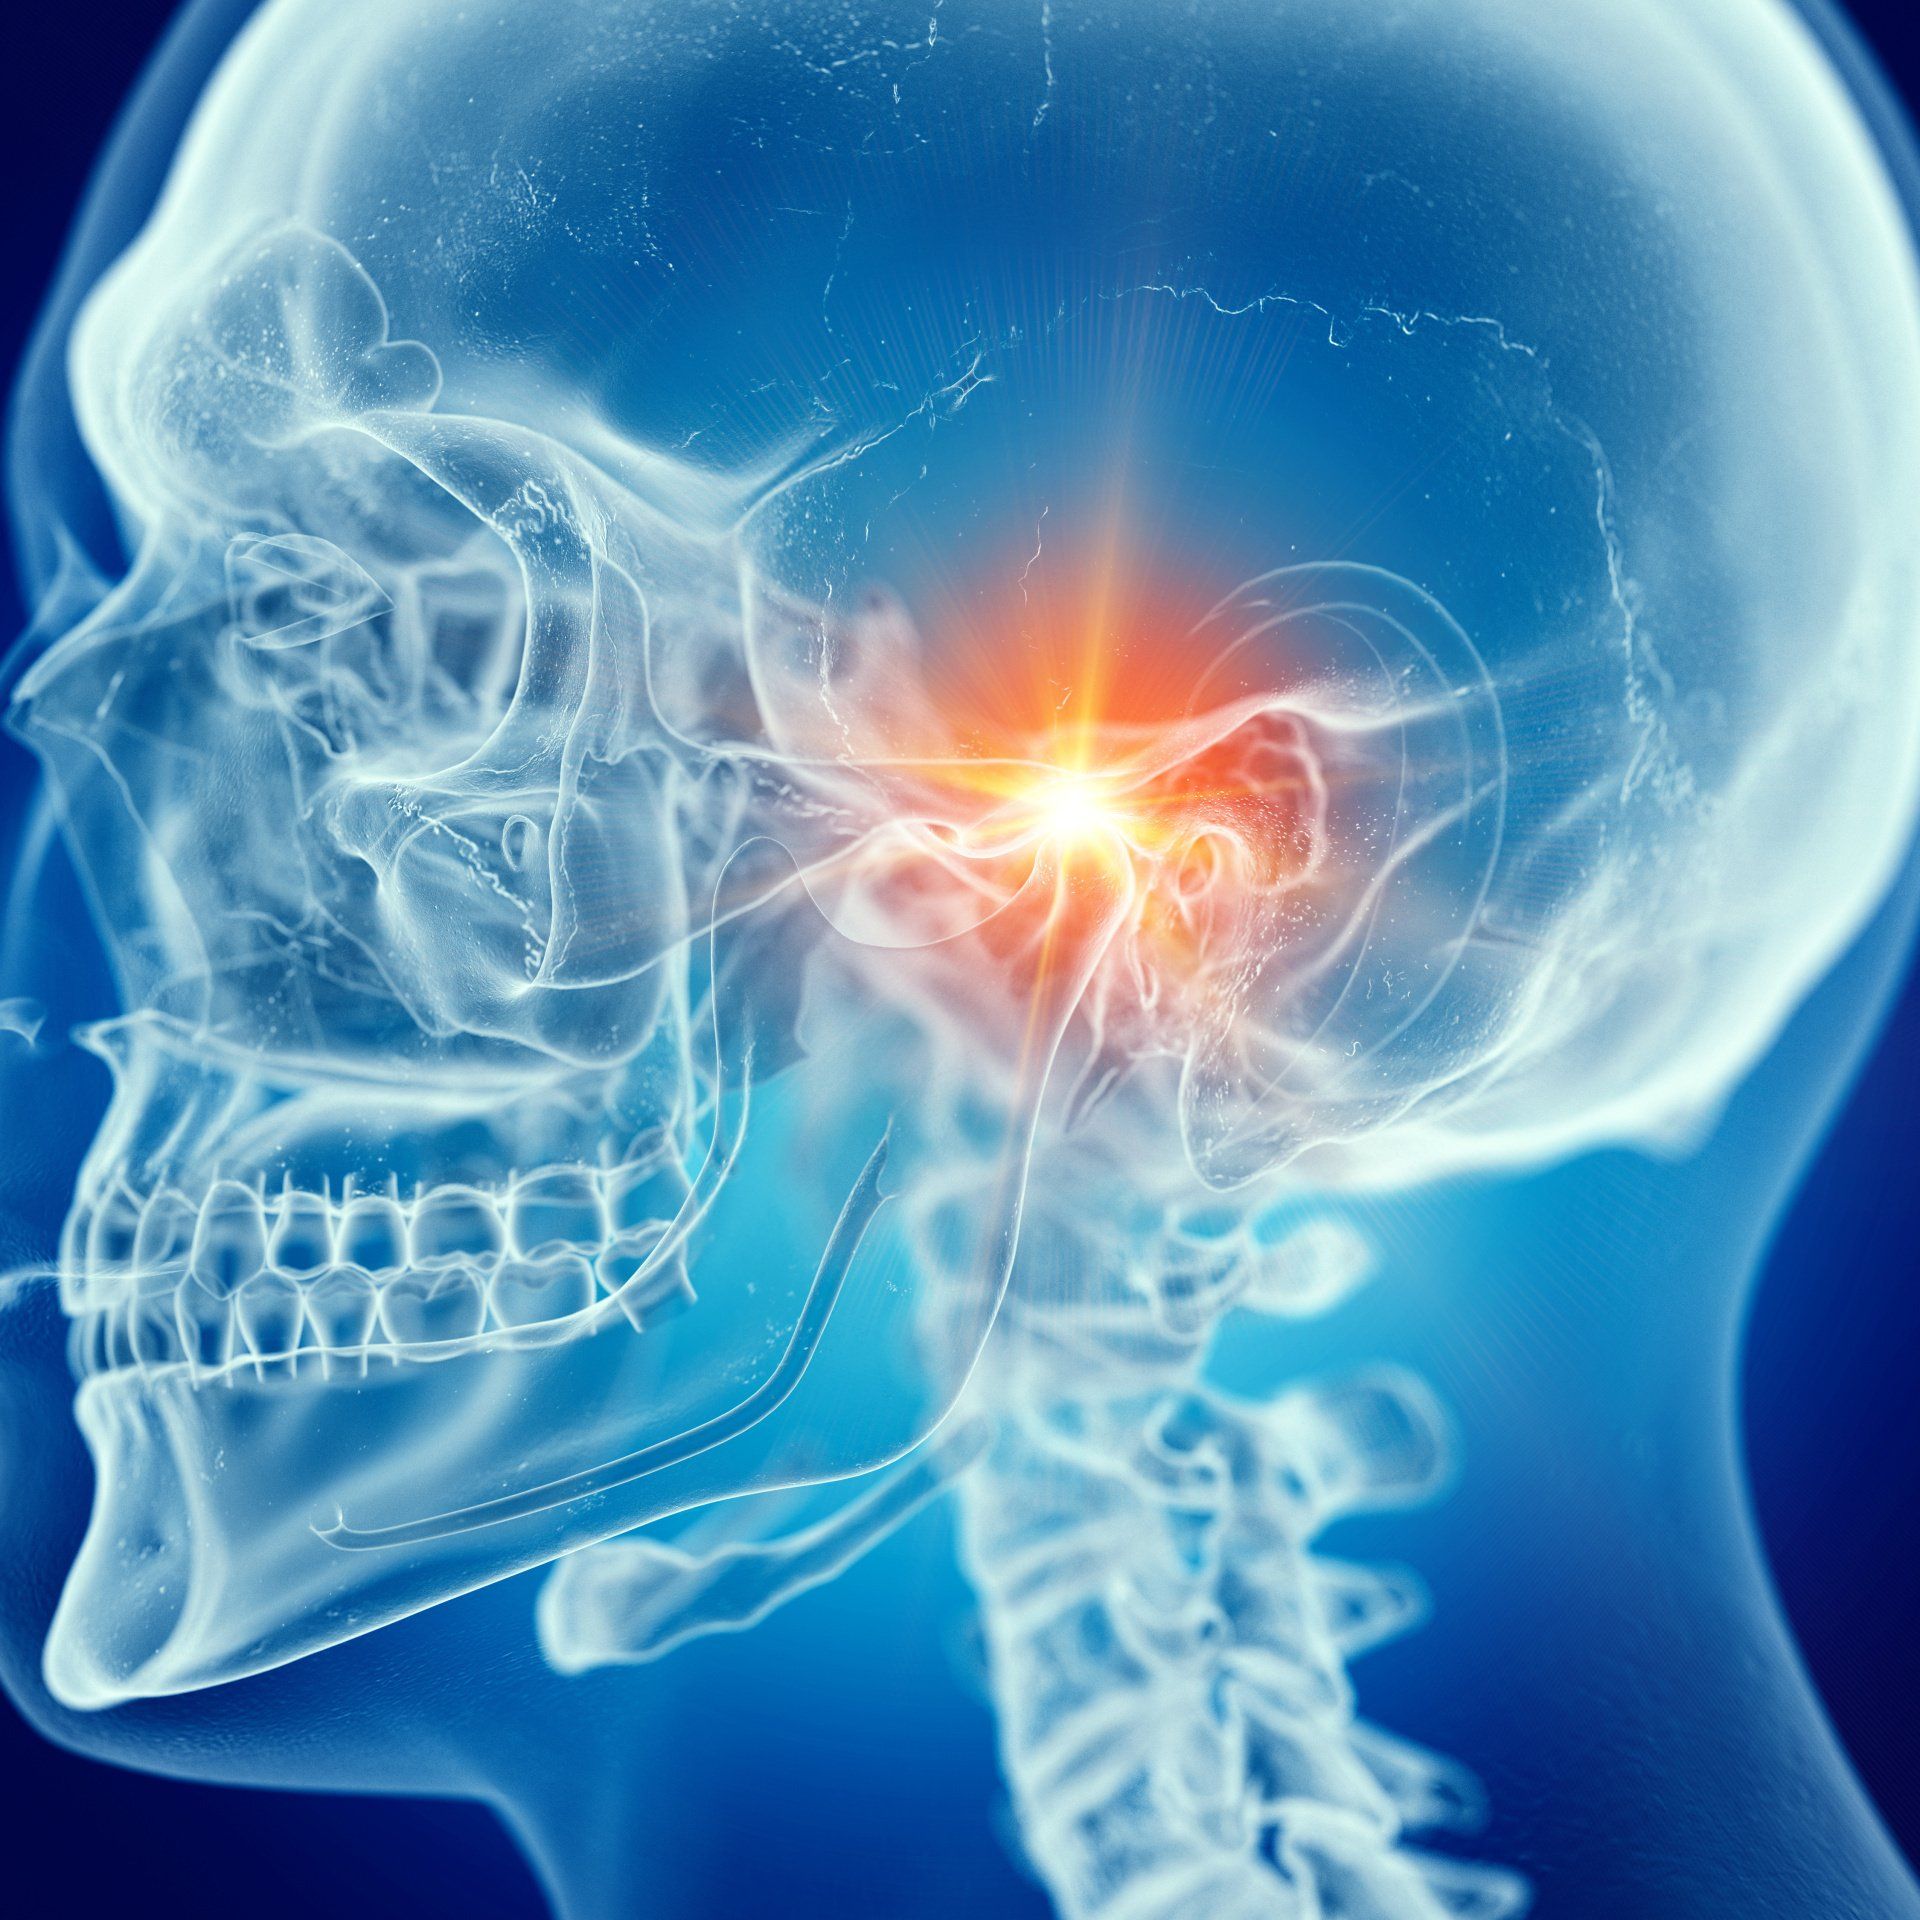

-  Als lokal auslösende Faktoren gelten schief stehende Zähne, . . .. . . schlecht passender Zahnersatz oder störende Füllungen, ebenso wie Fehlstellungen des Ober- und Unterkiefers. In Fällen, in denen das Knirschen und Pressen einhergeht mit Funktionsstörungen des Kausystems, spricht man von einer CMD, der Cranio-Mandibulären-Dysfunktion, bei der die Harmonie des gesamten Bewegungs- und Stützapparates beeinträchtigt ist. Häufig wird diese begleitet von Schmerzen im Kiefergelenk, der Kaumuskulatur sowie der angrenzenden Muskulatur im Schulter-Nacken-Bereich.